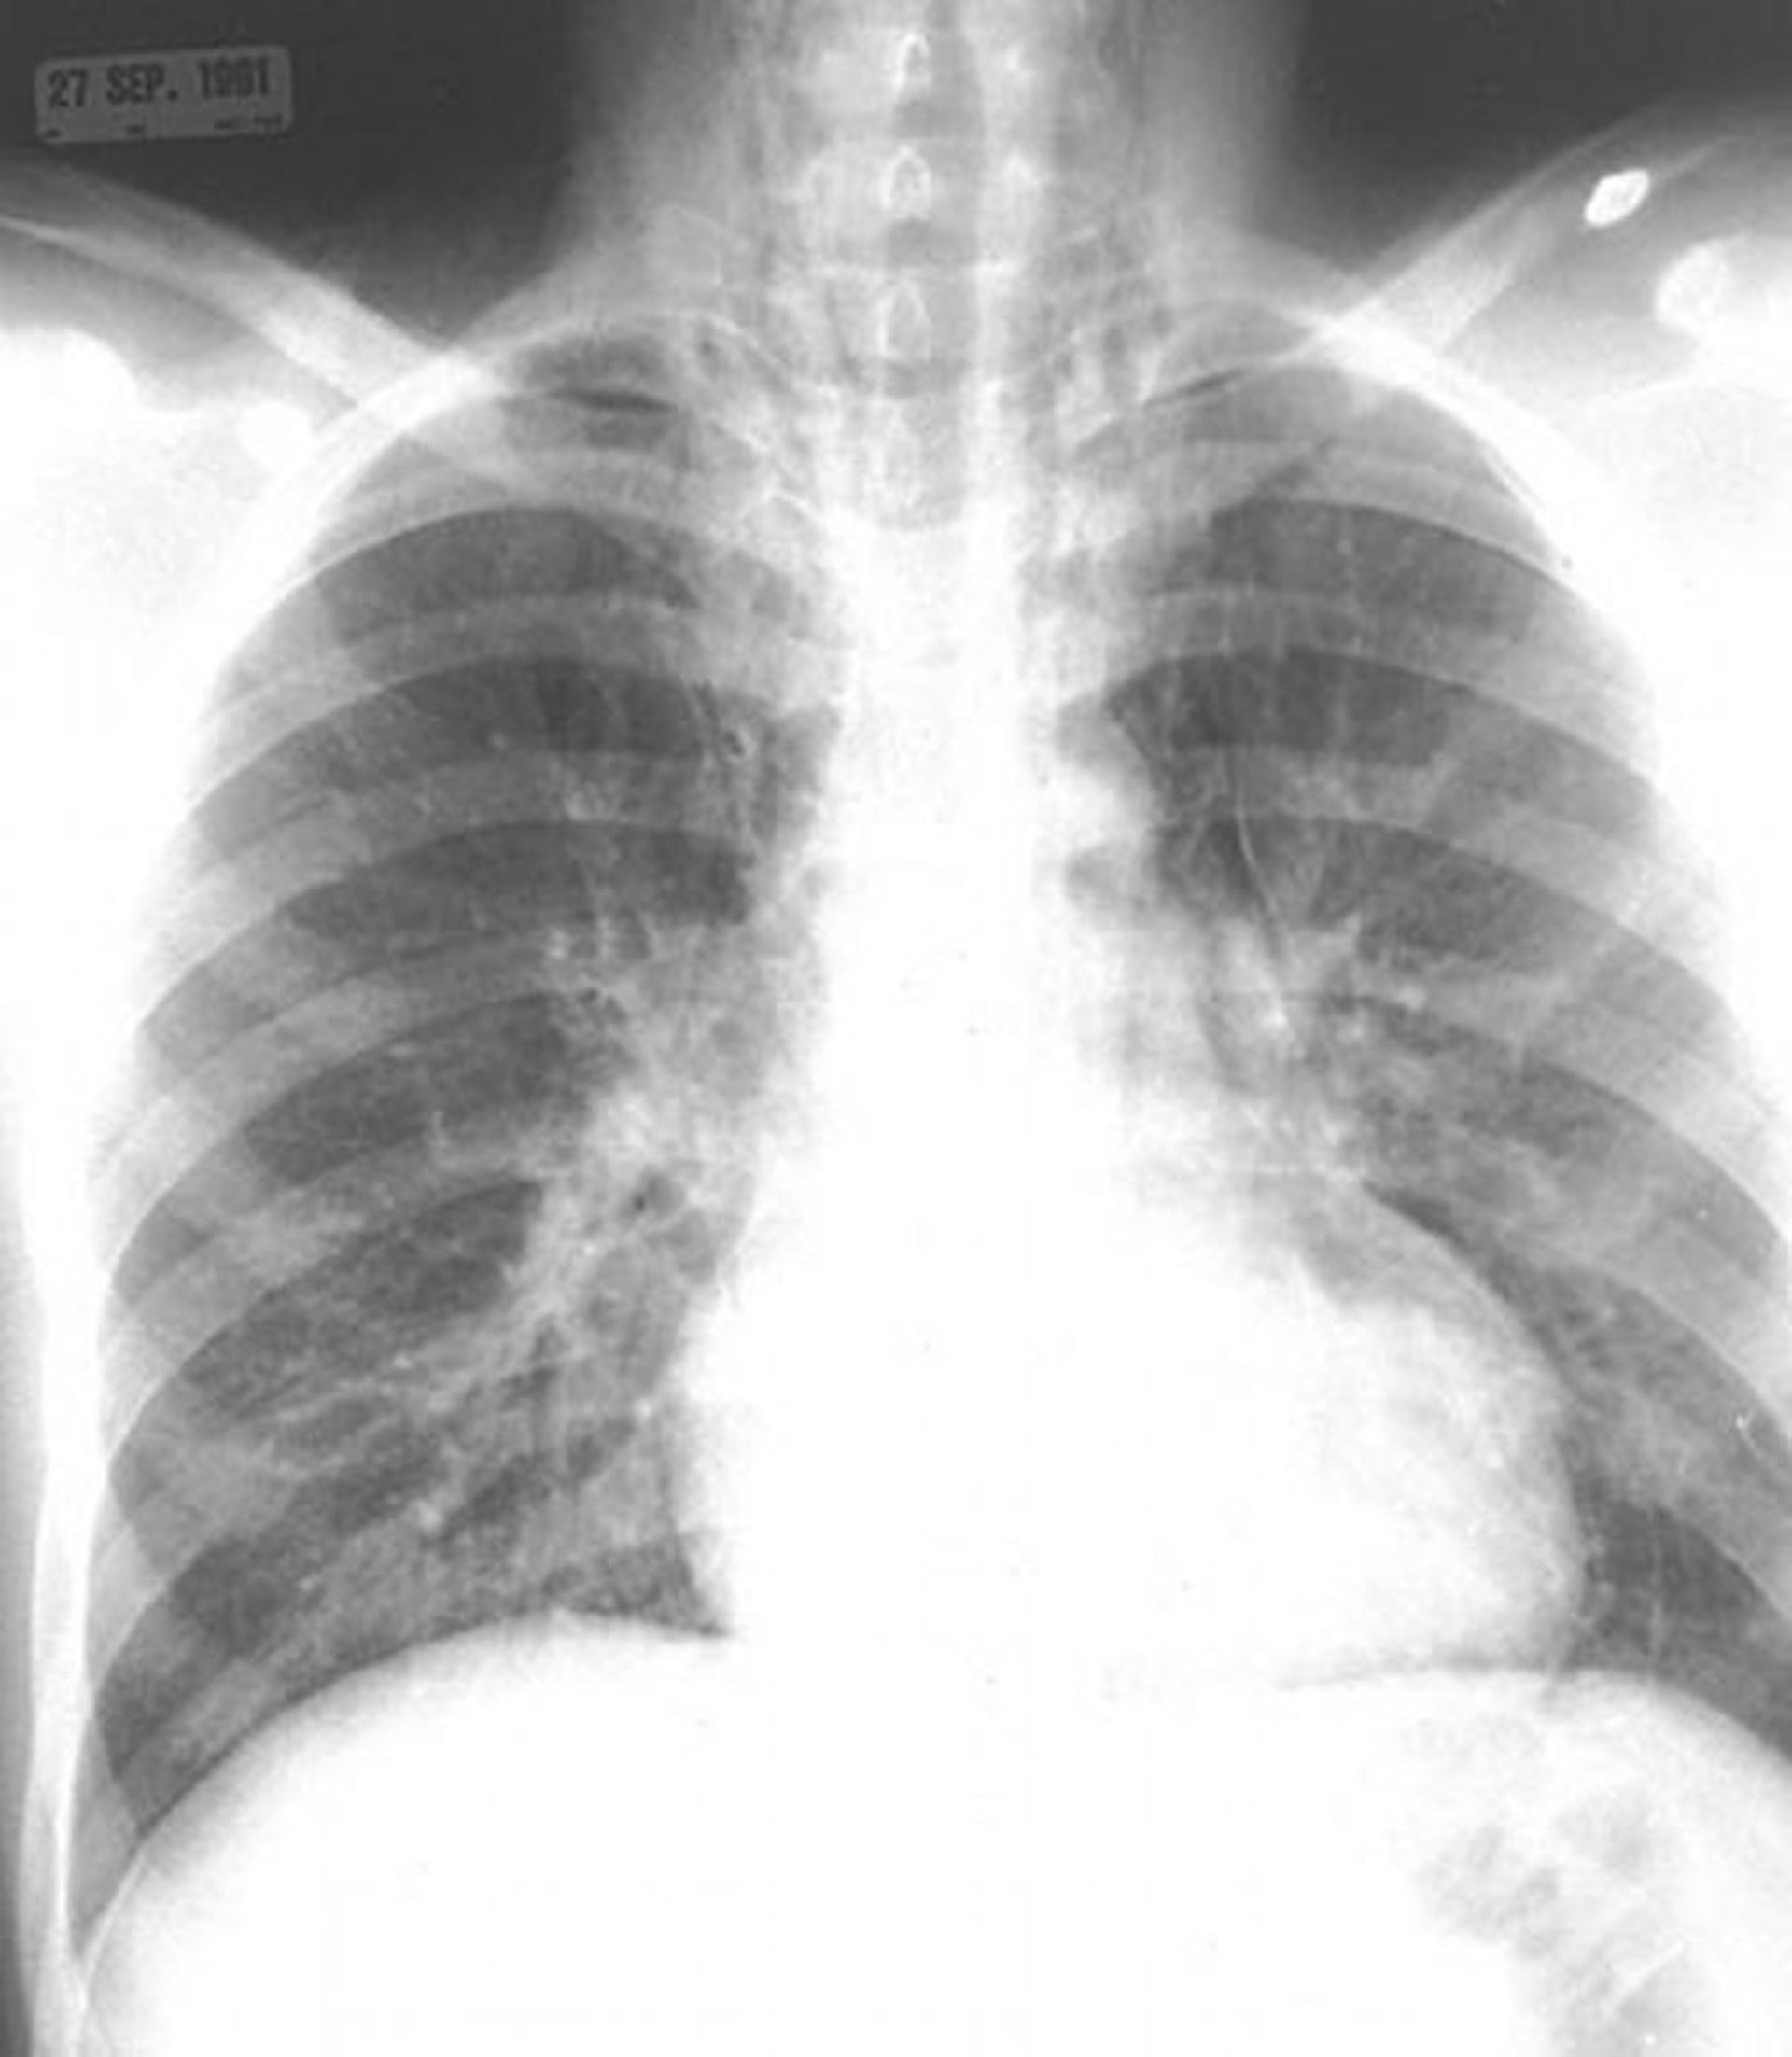

Пневмомедиастинум

Обращаем внимание на наличие воздуха в средостении и в мягких тканях шеи.